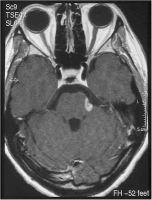

Abbildung

Enzephalitischer Plaque - Nervus trigeminus

Abbildung 1: MRT mit enzephalitischer Plaque in der Eintrittszone des Nervus trigeminus links.

Keywords: Enzephalitischer PlaqueMRTNervus trigeminusNeurochirurgie